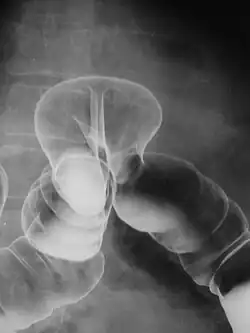

Raio-X de hérnia de cólon

De longe, as hérnias mais comuns (até 75% de todas as hérnias abdominais) são as chamadas hérnias inguinais. As hérnias inguinais são ainda divididas na hérnia inguinal indireta mais comum (2/3, representada aqui), na qual o canal inguinal é inserido através de uma fraqueza congênita em sua entrada (o anel inguinal interno) e o tipo de hérnia inguinal direta (1/3), onde o conteúdo da hérnia passa por um ponto fraco na parede traseira do canal inguinal. As hérnias inguinais são o tipo mais comum de hérnia em homens e mulheres. Em alguns casos selecionados, eles podem exigir cirurgia. Há casos especiais em que a hérnia pode conter hérnia direta e indireta simultaneamente hérnia pantalonariana, ou, embora muito rara, pode conter hérnias indiretas simultâneas.[15]